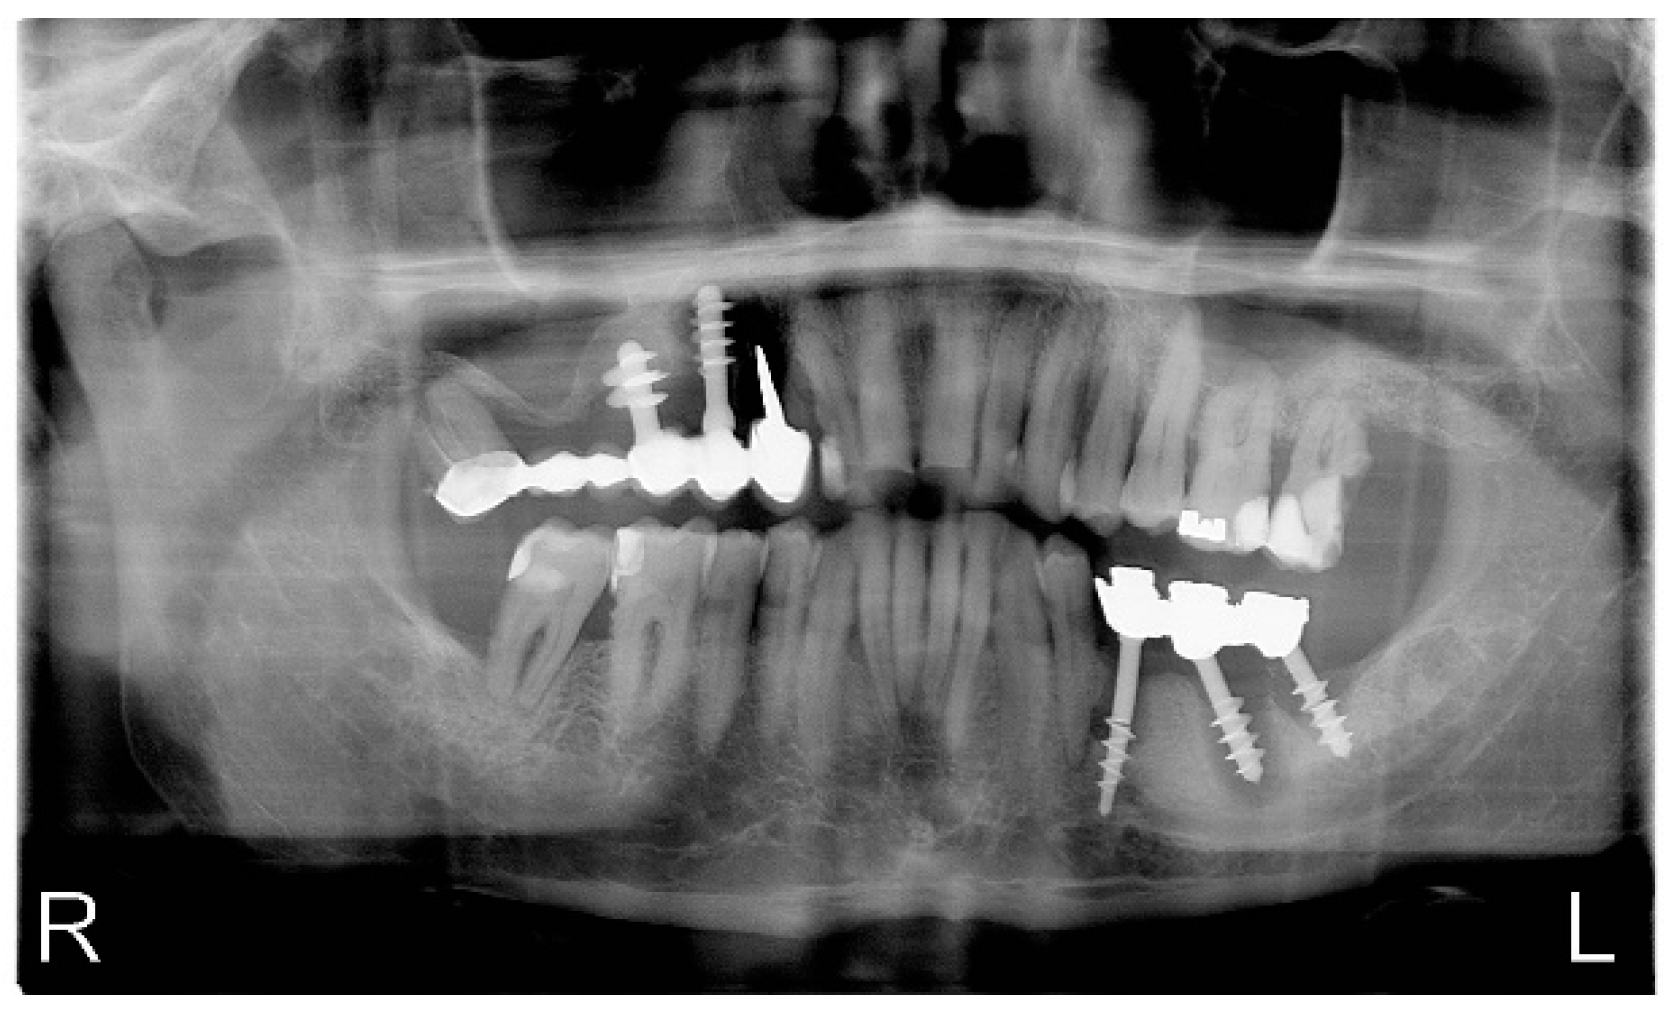

4. Case Report